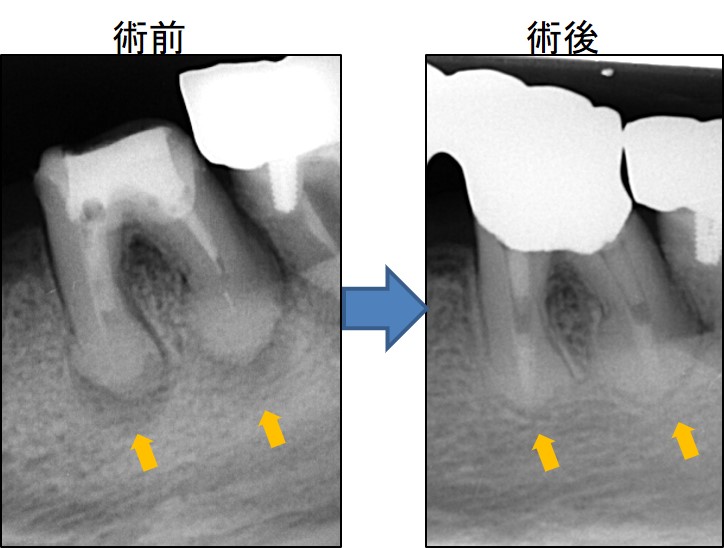

同じく、下写真も左が術前、右が術後です。

術前の黒い影(オレンジ矢印)が術後で改善しています。

今回のケースは、歯周病のように歯の周囲から細菌感染が起きたわけではなく、歯の中から細菌感染しています。このような場合、金属冠を外して根の中の消毒を行う必要があります。